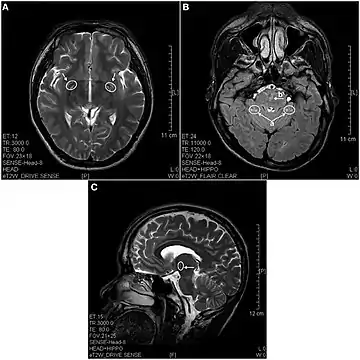

In 2013 a study using magnetic resonance imaging showed brain lesions in ketamine addicts (using from 0.2g twice a week up to 1g daily for 0.5 up to 12 years) with severity depending on the duration of addiction and daily intake of ketamine. Cortical atrophy and holes in superficial white matter are seen early on. After 4 years of addiction lesions spread throughout the brain and damage is evident in the pons and other deeper brain structures.[17]